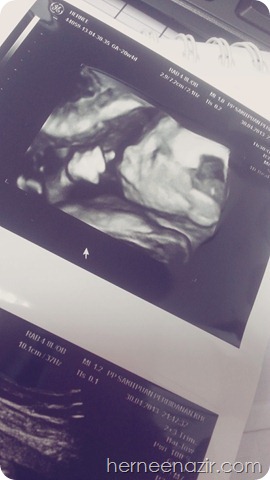

ok gambar adik baby ni masa check up 30/4 kat khor & loh..

hamboiiiiiiiiiiiiiiiiiiii..

baby ni aktif benor.. dah 2 kali tunjuk jantina..

tak payah nak sorok2 dengan ummi, babah n abang ilham lagi..

dah konfem boboiboy..

tengok tu..

dia tengah syok hisap jari tau masa ni..

geramnya..sambil flying kick kat ummi..